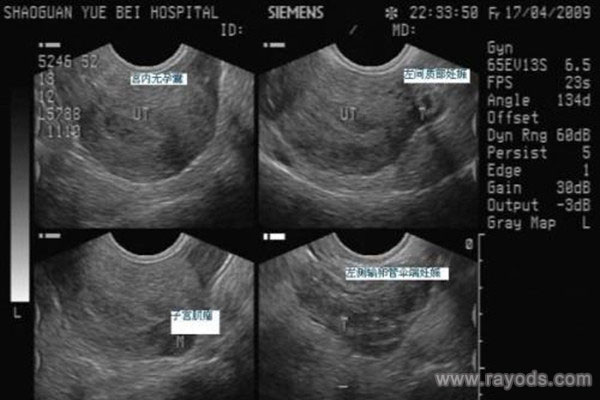

3、B超(超声波)诊断

用B超检测宫外孕,准确性比较高,是目前医院常用的方法。宫外孕是子宫以外的妊娠情况,正常妊娠停经7周时,用B超方能查到胚芽与原始心管搏动。如果探查不到的话,可以结合HCG测定是否宫外孕。